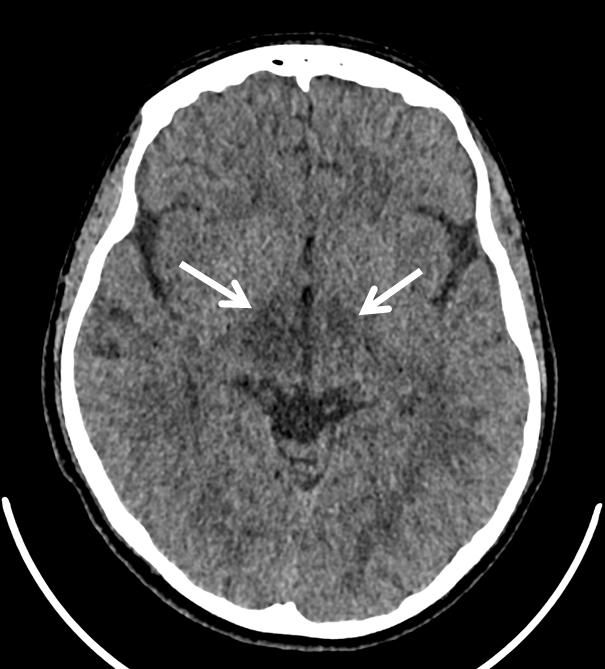

Video EEG at our institution did not demonstrate evidence of seizures. Head computed tomography (CT) on admission showed hypoattenuation in bilateral thalami, though more on the right side as compared to the left side. Magnetic resonance imaging (MRI), magnetic resonance angiogram, and magnetic resonance venography were done given concern for vasculitis and significant for hyperintensity flair in the medial thalami/massa intermedia. Urine toxicology screen was negative. A lumbar puncture showed a high opening pressure and cerebrospinal fluid (CSF) pleocytosis with white blood cells of 26, suggesting infectious versus autoimmune processes. Further infectious work-up, including a complete blood count, procalcitonin, meningitis/encephalitis panel, antistreptolysin O (ASO) titer, group A streptococcus direct DNA probe, rapid plasma regain (RPR), Epstein-Barr virus, Lyme disease titers, HIV, quantiferon gold, Bartonella antibodies, and herpes simplex virus (HSV) antibodies were all negative. Rheumatologic workup, including erythrocyte sedimentation rate, c-reactive protein, antinuclear antibody, anti-ds DNA, C3, C4, proteinase-3 antibody, myeloperoxide antibody, and centromere antibody were unrevealing. A comprehensive metabolic panel, lactic acid, ammonia, thyroid stimulating hormone (TSH), free T4, vitamin B1, ceruloplasmin, and copper studies did not demonstrate a toxic or metabolic cause. A CT abdomen and pelvis was done to rule out an oncologic process and was within normal limits. Alpha-fetoprotein was normal. An autoimmune and paraneoplastic panel was sent from the CSF, however results were not available during the patient’s hospital admission.

Laboratory evaluation was largely unrevealing, except for slight CSF pleocytosis. This, along with the CT and MRI findings and the clinical picture of waxing and waning aggression, agitation, and insomnia was concerning for autoimmune encephalitis. One week after discharge, CSF studies returned positive for anti-NMDAR and anti-MOG antibodies.

Figure 1